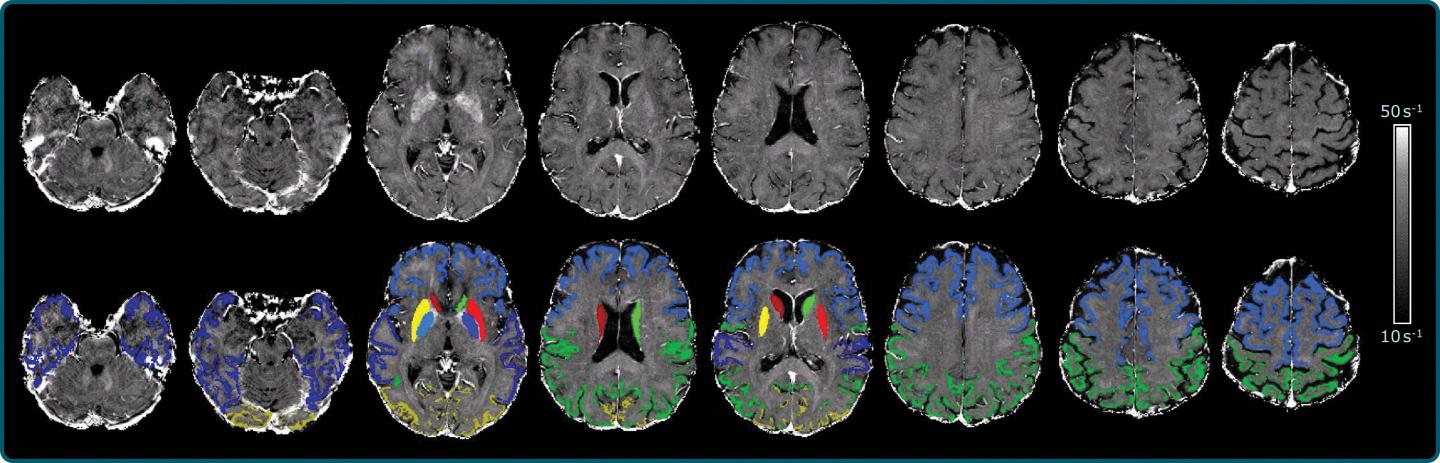

For the new study, Dr. Schmidt and colleagues developed an approach using a 3T MRI scanner that allowed the best tradeoff between resolution and scan time, along with postprocessing to correct the influence of the distortions.

The technique enabled the researchers to create a map of brain iron, determining iron levels in parts of the brain like the temporal lobes, or the areas of the brain lying underneath the temples, and the occipital lobes in the back of the head.

"We found indications of higher iron deposition in the deep gray matter and total neocortex, and regionally in temporal and occipital lobes, in Alzheimer's disease patients compared with age-matched healthy individuals," Dr. Schmidt said.